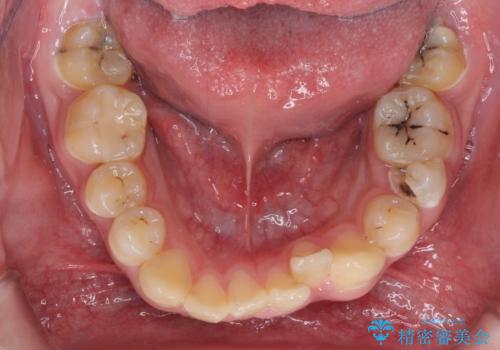

前歯のデコボコとむし歯だらけの歯列 矯正治療と虫歯治療

- むし歯が多く、歯並びも悪いとのことで、以前通院されていたご家族の紹介で来院された患者様です。

口腔内に無頓着であったため、まずはしっかりと歯磨きトレーニングを行い、必要な虫歯治療を行いました。

矯正治療は、むし歯が酷く抜歯が望ましい歯を1本抜歯して、ワイヤー装置にて整えることとしました。